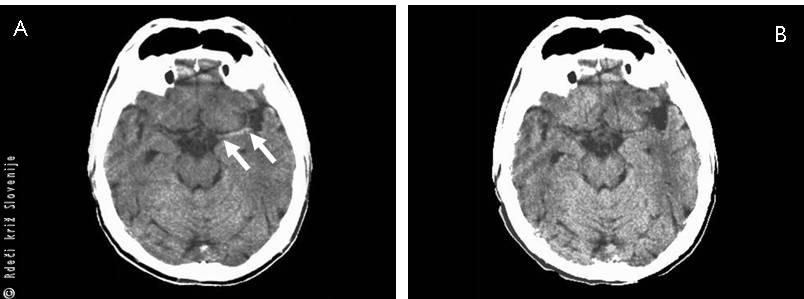

Slika 6

A – Shematski prikaz mesta nastanka možganske krvavitve.

B – Vzrok za nastanek možganske krvavitve – razpok arterije v možganih, ki ima spremenjeno steno žile (mikroanevrizma) zaradi povišanega krvnega tlaka.

C – Računalniška tomografija možganske krvavitve.

Slika 7

A, B – Računalniško tomografska slika subarahnoidne krvavitve.

C – Vzrok za nastanek subarahnoidne krvavitve – anevrizma.